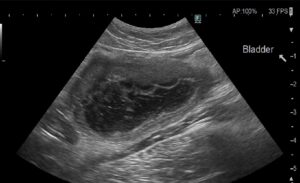

※膀胱の壁が分厚く腫れ、膀胱の中には汚れがたくさん浮いています(11/21)

この子は、以前から膀胱炎を繰り返していたため、膀胱内部がかなり炎症を起こし、粘膜が腫れていました。

さらに、過去に起こした膀胱炎の影響と思われますが、尿道から出てこられない大きさの汚れ

(血餅や、膀胱粘膜が壊死して剥がれ落ちたもの)が膀胱内に多数認められました。

白く浮いたようにみえるものが汚れです(11/22)